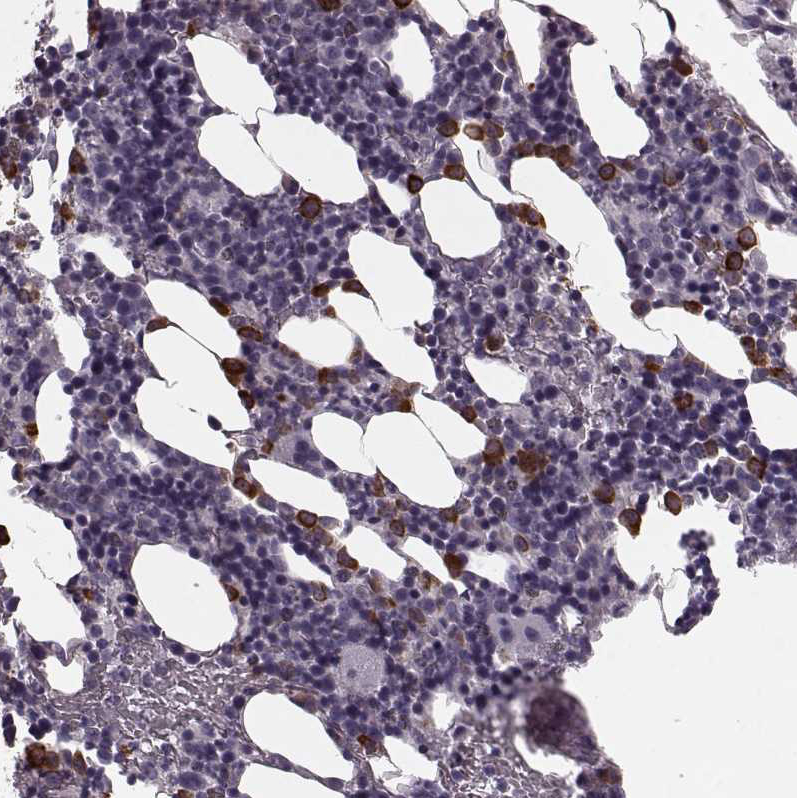

Immunohistochemistry analysis in human bone marrow and skeletal muscle tissues using HPA040442 antibody. Corresponding CST7 RNA-seq data are presented for the same tissues.